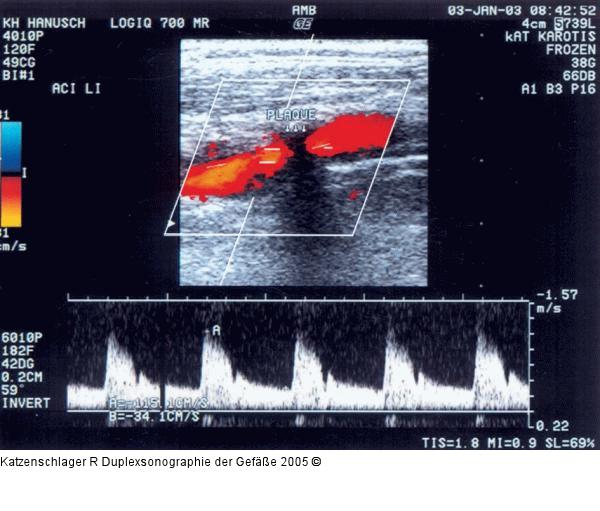

Abbildung 7a: Duplexsonographie - Karotis Kalkhältige Plaque, die die ACI links etwa 25–50 % stenosiert (Vmax 1,15/0,3 m/sec) |

Kalkhältige Plaque, die die ACI links etwa 25–50 % stenosiert (Vmax 1,15/0,3 m/sec) |